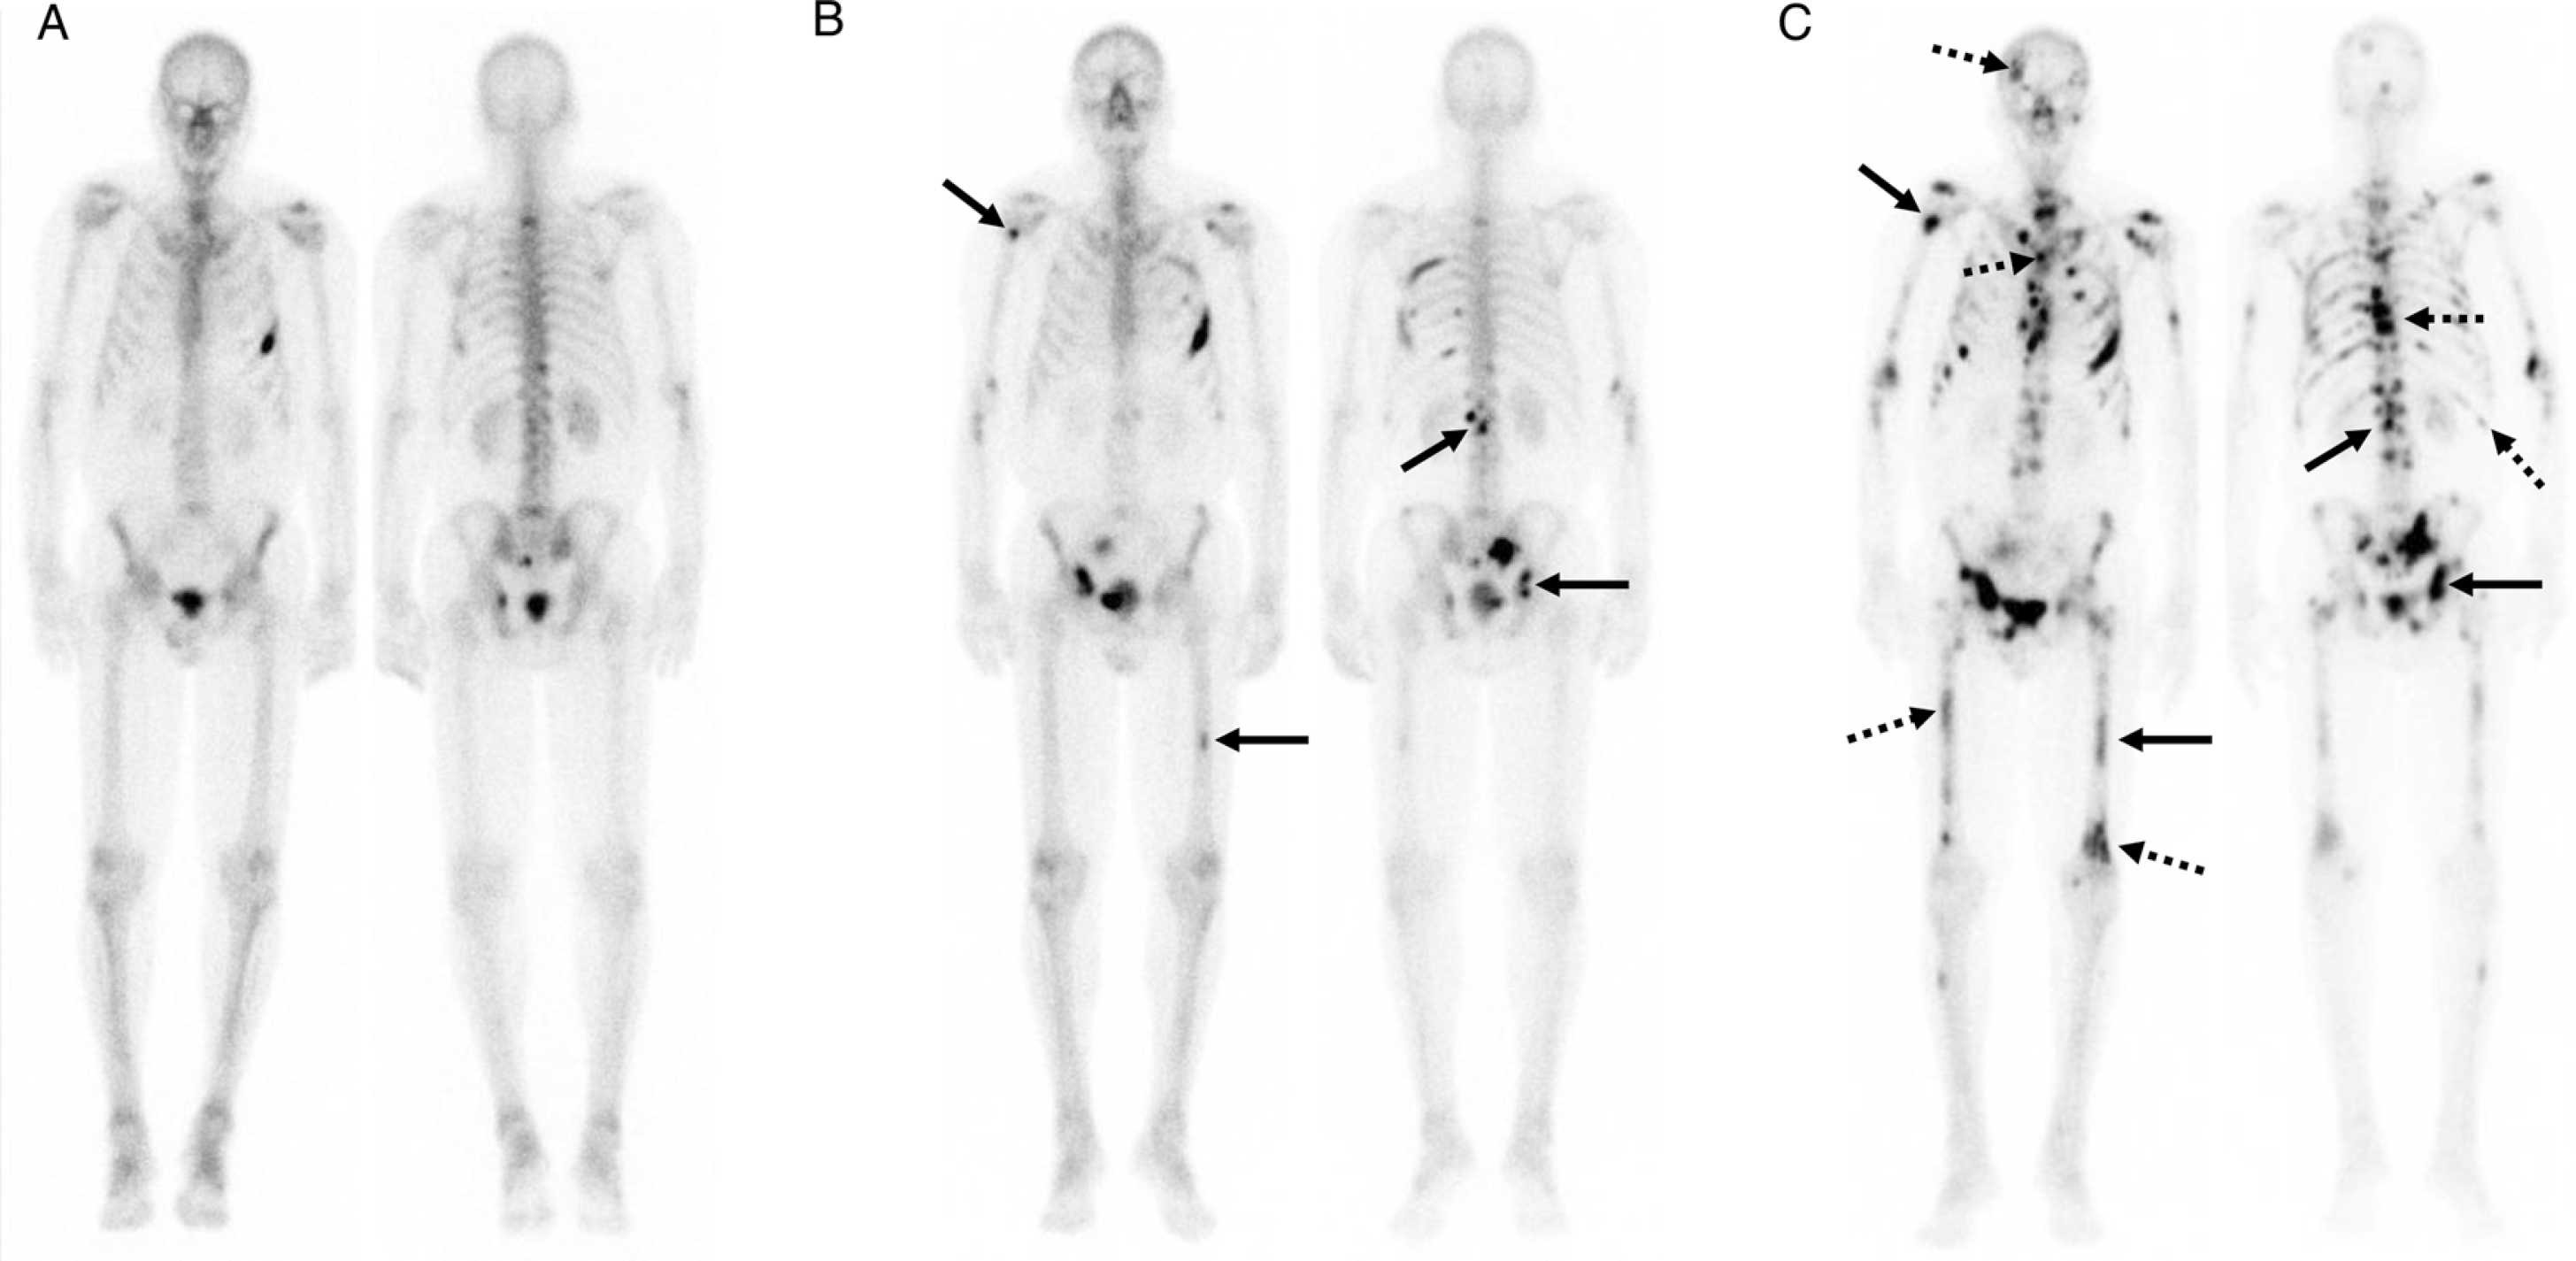

Imaging response assessment figureImaging response assessment for oncology: An algorithmic approach

Kathleen Ruchalskia, Rohit Dewana, Victor Saia, Lacey J.McIntosh, MartaBraschi-Amirfarzanc. Dr. Lacey McIntosh co-authored a paper with other cancer imagers from UCLA and Lahey/Tufts on an algorithmic approach for imaging response assessment in oncology patients that was just published in the European Journal of Radiology Open!

Imaging response assessment for oncology: An algorithmic approach

June 07, 2022. Author(s): Kathleen Ruchalski, Rohit Dewan, Victor Sai, Lacey J. McIntosh, Marta Braschi-Amirfarzan. Source: European journal of radiology open